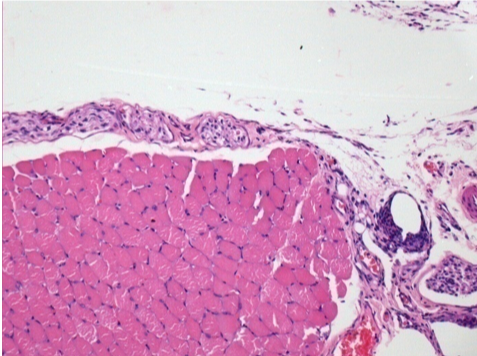

10 días después de la inyección de Endopeel

10 días después de la inyección de Endopeel 0,1 ml en el músculo pretibial derecho.

Aquí puede ver la formación de las vacuolas que están rodeadas de linfocitos. Las vacuolas son diferentes a la necrosis tisular. La presencia de linfocitos está relacionada con la permeabilidad de las membranas celulares.

L : Control-100xD10

R:100xD10

R :200xD10

R :400xD10